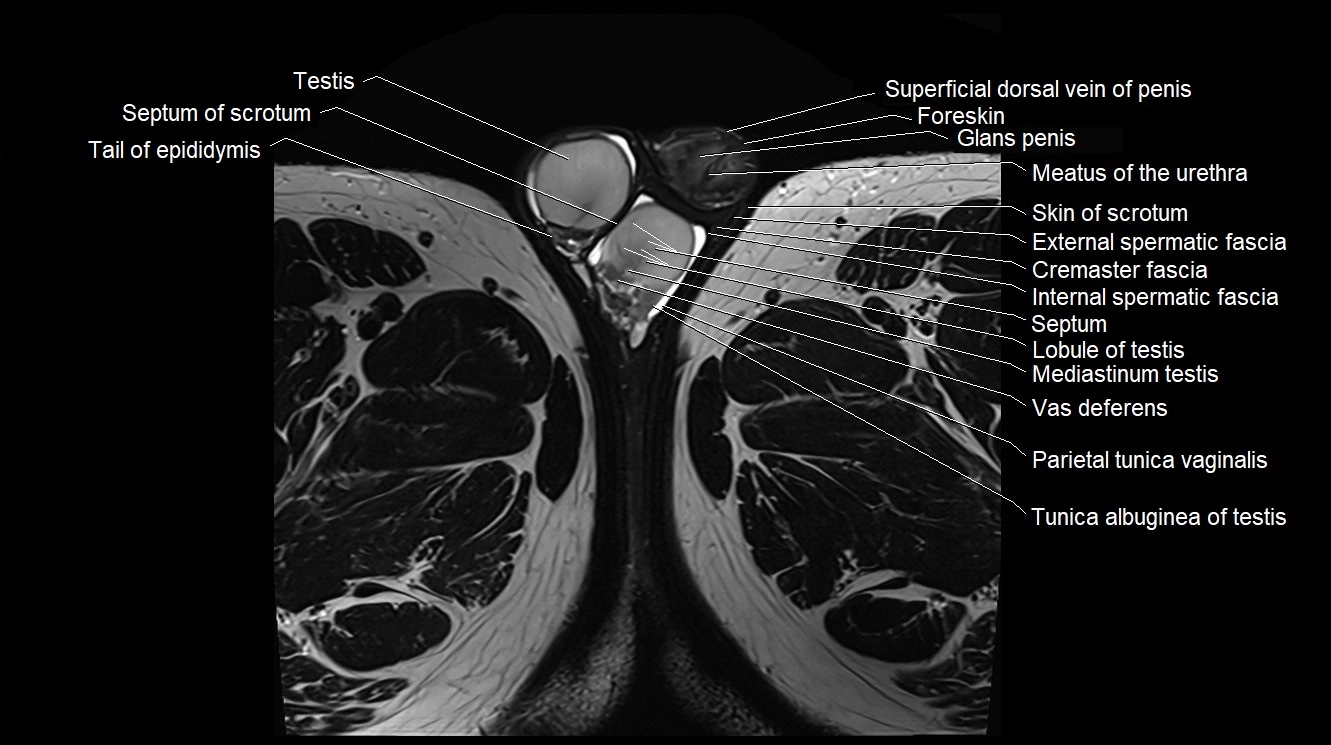

- Body of epididymis

- Epididymis

- Foreskin

- Glans penis

- Head of epididymis

- Internal spermatic fascia

- Lobule of testis

- Meatus of the urethra

- Mediastinum testis

- Membranous urethra

- Parietal tunica vaginalis

- Septum of scrotum

- Skin of scrotum

- Superficial dorsal vein of penis

- Tail of epididymis

- Testis

- Tunica albuginea of testis

- Vas deferens

- Visceral tunica vaginalis